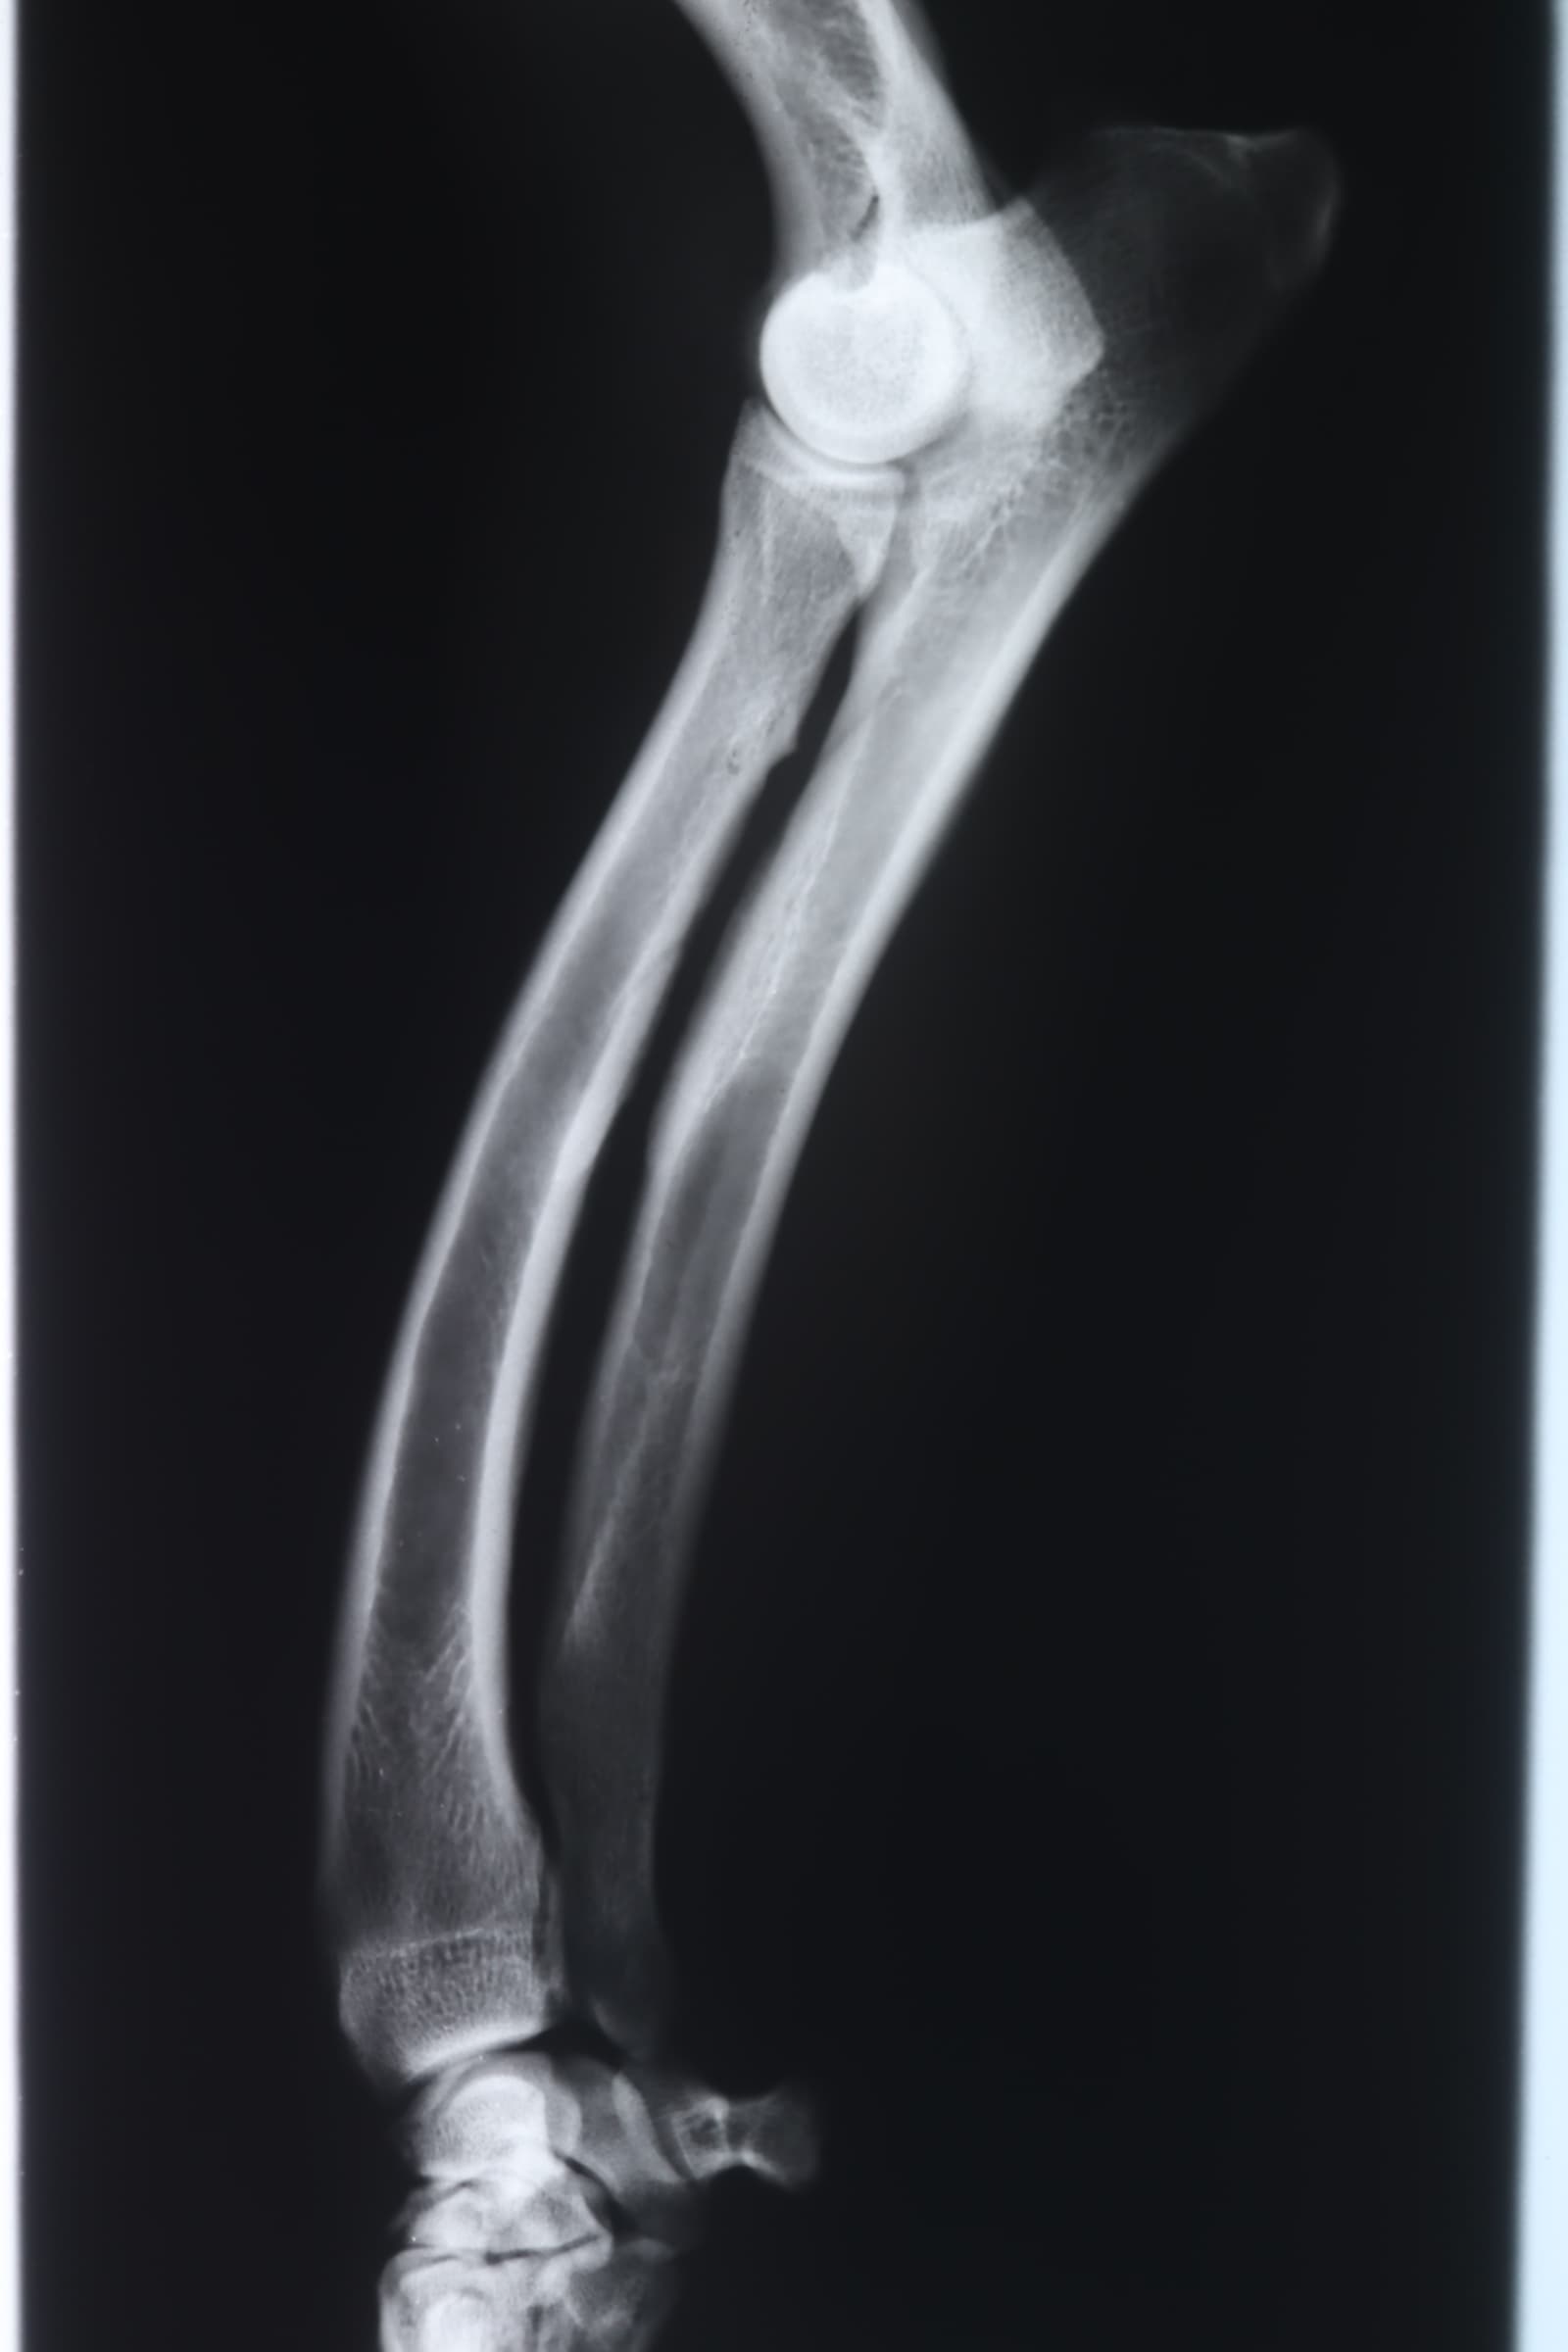

レントゲン検査

前足が曲がっているためレントゲン検査をしました。おそらく、子犬のときに足を痛めた影響で、二本の骨の一本ががうまく成長しなかったようです。

痛めた方はの骨が成長の衰え、一方は正常に成長しようとするので、足が曲がってしまっています。幸いなことに、それは軽度なので、症状があまりありません。重症な場合は、肘関節が外れてしまうことがあります。(2024年10月24日)